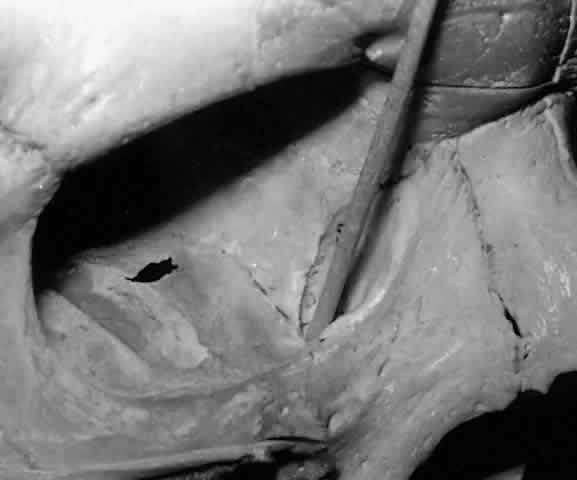

The lacrimal bone is pneumatized by anterior ethmoidal air cells (agger nasi bullae), which occasionally pneumatizes the anterior lacrimal crest. In cases where the lacrimal bone contribution to the lacrimal fossa is dominant (Fig. 27), ethmoidal air cells are more likely to be found in the lacrimal fossa and nasal cavity.19,28 Clinically these air cells separating the upper half of the lacrimal fossa from the nasal cavity, if present, must be opened or removed in order to enter the nasal cavity during dacryocystorhinostomy surgery.

Fig. 27. Ethmoidal air cells extend to the anterior lacrimal crest (arrow), demonstrating a dominant ethmoidal and lacrimal bone contribution to the lacrimal fossa (left orbit).